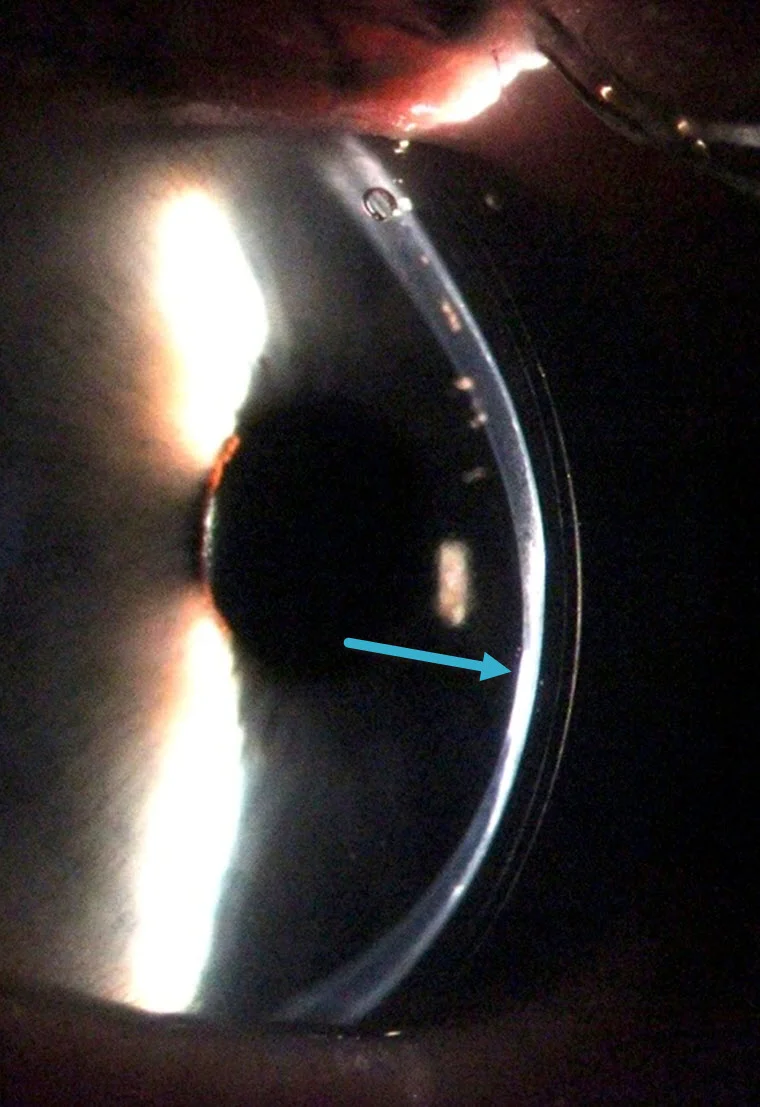

Hard contact lens for keratoconus Stock Image C009/0105 Science Keratoconus Contact Lenses Cost Uk Web contact lens fitting for keratoconus is done by our specially trained optometrists and needs great patience from both the. The cost per lens on the nhs is around £55; Web at zacks eye clinic in central london we have optometrists who specialise in treating keratoconus with specialist contact lenses. Web our photograph shows a comparison of a scleral lens. Keratoconus Contact Lenses Cost Uk.